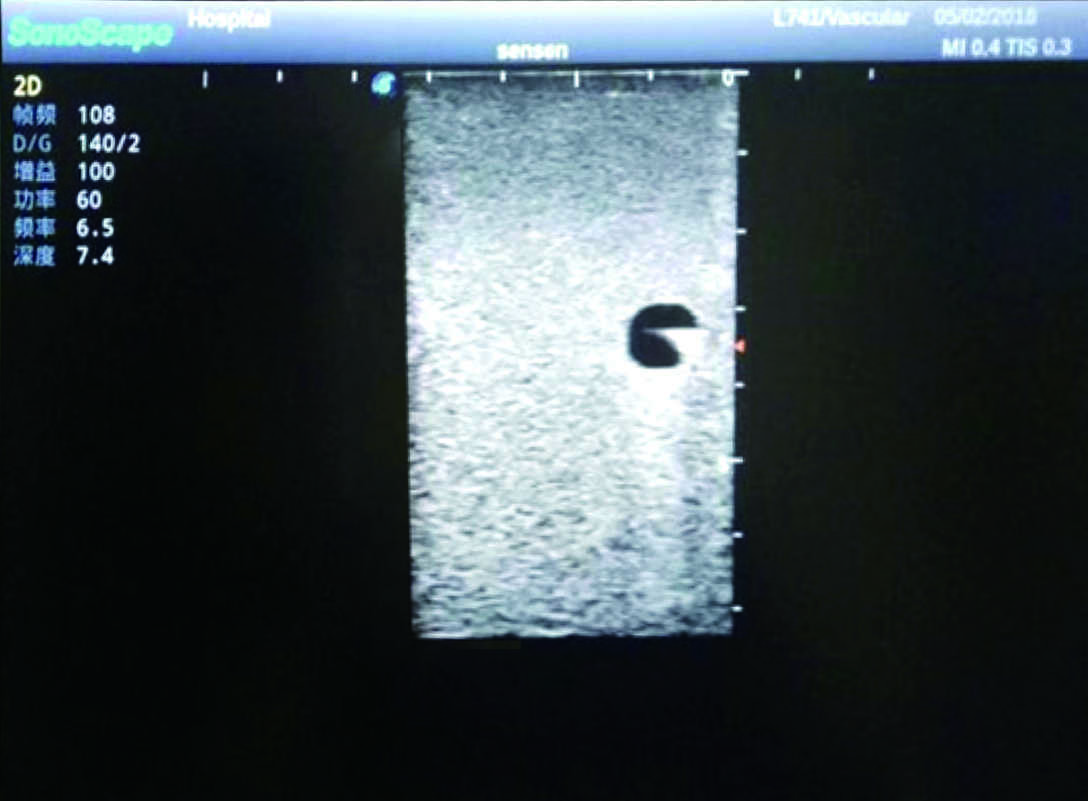

PICC Ultrasound Training Model

Model TYE1510.1

1)   Made of high molecular polymer ultrasound material, close to the real skin

2)   It can be used by real ultrasound machines

3)   Clear and real images of the tissues and organs (basilic vein and superior vena cava)